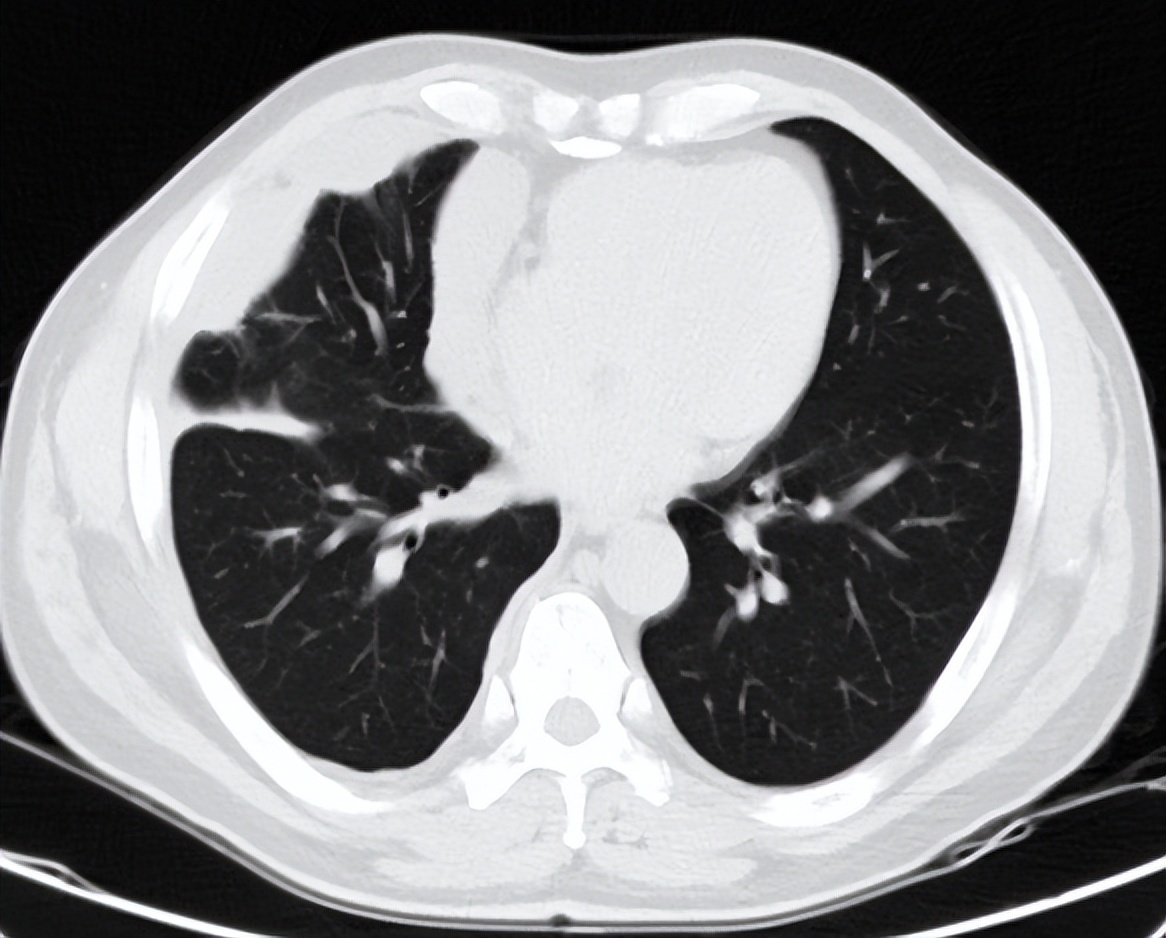

患者2020.6.16入院完善相关检查,评估疗效PD,考虑到二线化疗推荐吉西他滨,既往联合铂类也获得了不错的疗效,于2020-6-18至2020-9-21行二线化疗GP(吉西他滨1.8gD1、8+奈达铂45mgD1-3)方案化疗共4周期,后于2020-10-21行G-T1(吉西他滨1.8g)单药维持化疗。

2021-5-21日入院后完善相关检查,胸部CT检查提示病灶进展,后予以化疗+抗血管治疗(白蛋白紫杉醇480mgd1+贝伐珠单抗600mg)治疗,并行右侧胸膜SBRT治疗(40Gy/5F),治疗周期为8周期,最佳疗效为PR。